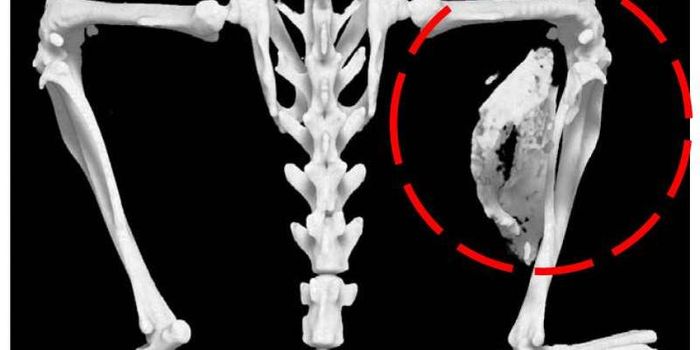

Follow a curation of discoveries and updates in immunology focusing on immune responses to infectious disease, structure and function, and developments in the defense against infection.